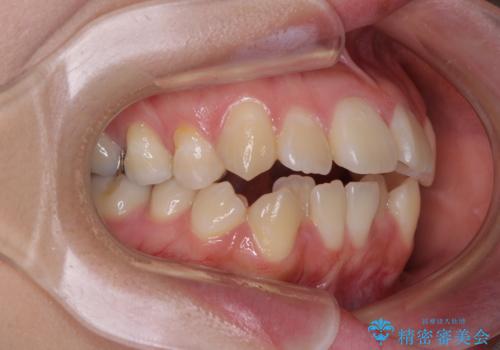

- 下の前歯のデコボコと、口元の突出感を改善したいと来院された患者様です。

突出感の強い上顎前歯をしっかりと後方移動させるため、上顎の裏側の補助装置(リンガルアーチ)とアンカースクリューを併用しています。

上下左右の第一小臼歯を抜歯して、目立ちにくいワイヤー装置で矯正を行いました。